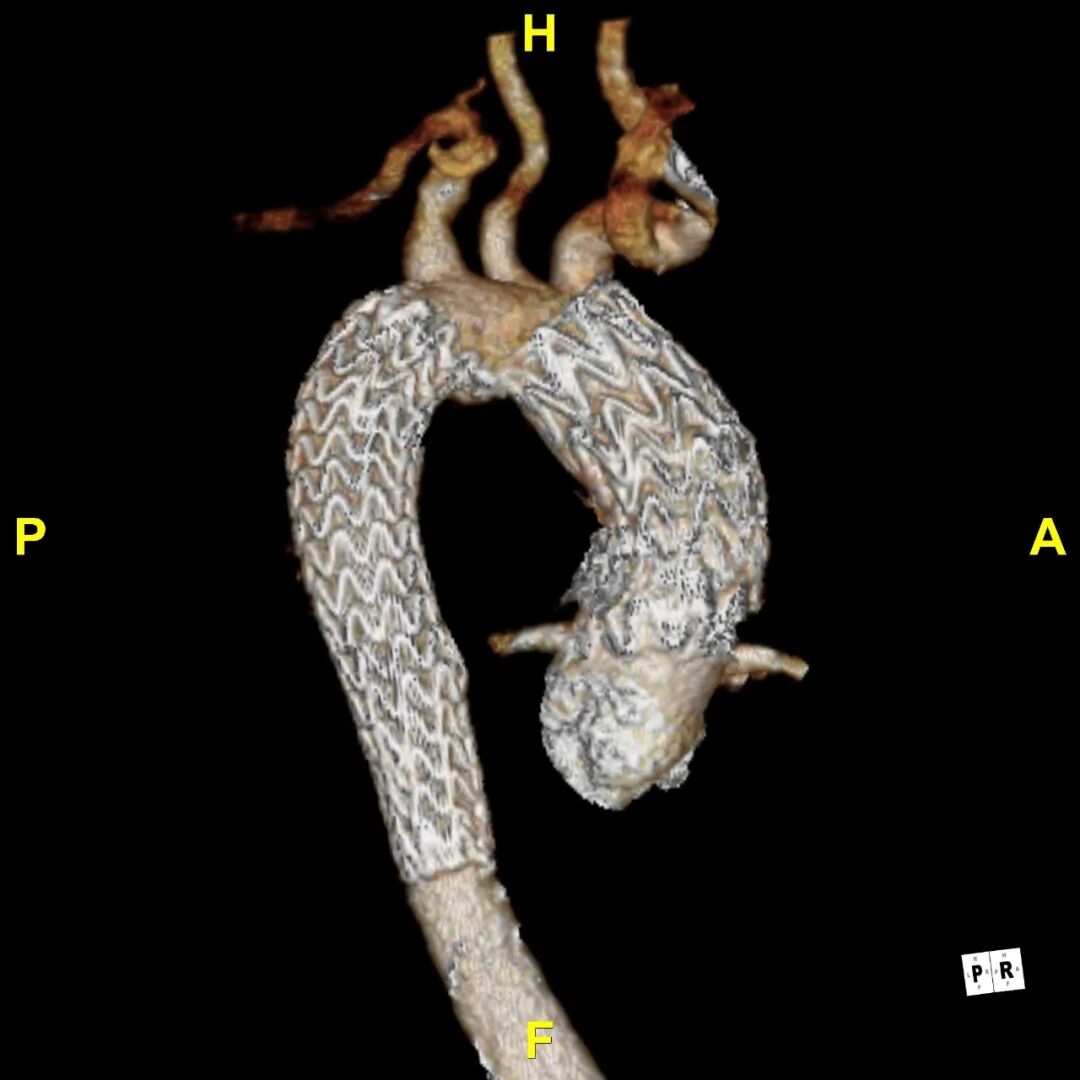

术后随访

患者出院前进行CTA复查,可见溃疡隔绝完全,弓上分支血管及冠状动脉通畅。

术后3D动态

术后3D动态 grey

术后3D重建